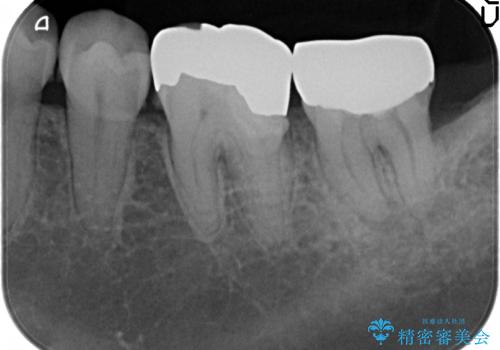

- 左下奥歯で咬むと違和感があるといらっしゃった方の症例です。

検査の結果左下7は失活(歯の神経が死んでいること)しておりX線上で根尖病変を認めたため、根管治療を行いました。

また左下6は遠心にあった歯茎より深い虫歯(縁下カリエス)の問題を解決するため、歯茎を下げる歯周外科手術を行いました。

歯周外科手術終了後、歯茎の回復を待ち左下6、7ともにオールセラミッククラウン(スタンダード)による補綴を行いました。